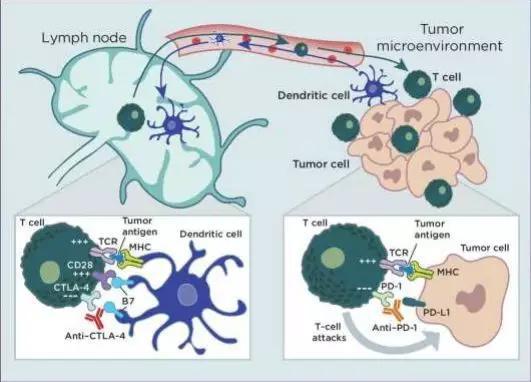

比如和生命息息相关的医学里,今年刚刚诺奖荣耀加身的免疫治疗,就是在以让人目不暇接的速度,飞快发展着自己的宽度和深度——一种种不断增加的适应症自然是宽度,而从治疗晚期患者到更早期更多样的用法,就是深度了。

免疫疗法,能不能再次超越放化疗呢?从理论上来说,免疫新辅助治疗也有不少优势,比如手术前患者的免疫系统更加完整,只是被肿瘤操纵,进入了明显的免疫抑制状态[4]。这样的话,PD-1/L1抑制剂们就不容易放空枪。

免疫治疗还可以利用手术前肿瘤体积大,新抗原多的特点,充分增强体内抗肿瘤免疫T细胞的活性,让它们分散到全身,清除微小的癌症转移灶,这比在辅助治疗时使用效果更好,优势已经在临床前期的动物实验中得到证实[5]。如果等到手术后再来做免疫治疗,随着免疫环境的变化,这些好处可能就减弱了。

在单药治疗和联合化疗之外,免疫治疗+免疫治疗也同样是一种思路,比如O药+抗CTLA-4的伊匹单抗。NEOSTAR试验就对比了联合免疫方案与O药单独使用三个周期的效果,不过31%的病理学显著缓解率似乎低于预期[15]。

比如用药次数和时机,新辅助治疗用几个周期才性价比最高,还不耽误手术的时间?而在免疫新辅助治疗时代,唱主角的也肯定不止PD-1/L1抑制剂们,搭配化疗药、抗CTLA-4单抗、抗血管生成药物甚至是放疗,也许都是有效的。